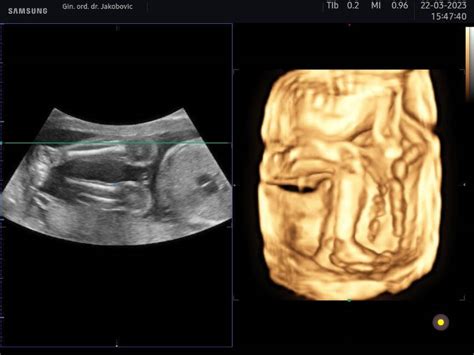

Zatiaľ čo 3D ultrazvuk poskytuje priestorový, ale statický obraz dieťatka, 4D ultrazvuk posúva túto technológiu o úroveň vyššie. Ide o zobrazenie plodu v pohybe, kde tretia dimenzia (priestor) je doplnená o štvrtú dimenziu - čas. Vďaka tomu rodičia môžu vidieť, ako sa ich bábätko v danom okamihu hýbe, naťahuje alebo dokonca zíva. Kvalita a detailnosť obrazu však závisí od viacerých faktorov, ako je spolupráca dieťatka a množstvo plodovej vody.

4D ultrazvuk nie je len o estetickom zážitku, ale predovšetkým o dôležitej diagnostike. Umožňuje lekárom detailne posúdiť anatómiu plodu, odhaliť prípadné vrodené chyby alebo anomálie a sledovať jeho vývoj. Pre rodičov je to zároveň neoceniteľná možnosť nadviazať hlbšie emocionálne spojenie so svojím nenarodeným dieťaťom ešte pred jeho príchodom na svet.